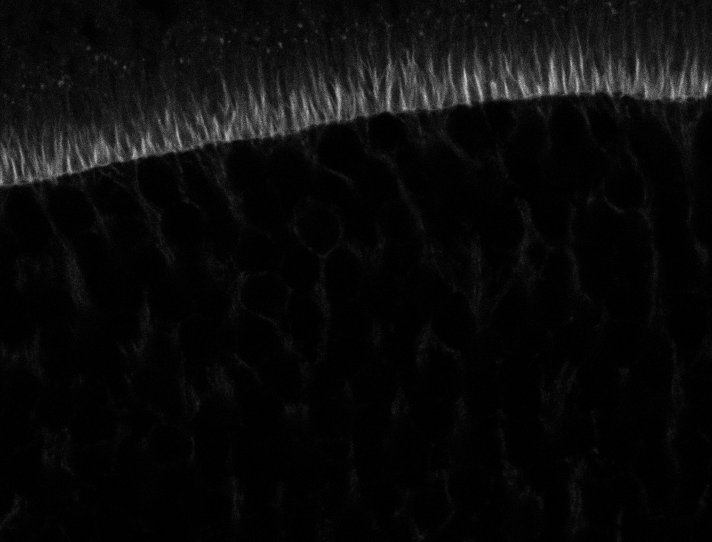

Actin